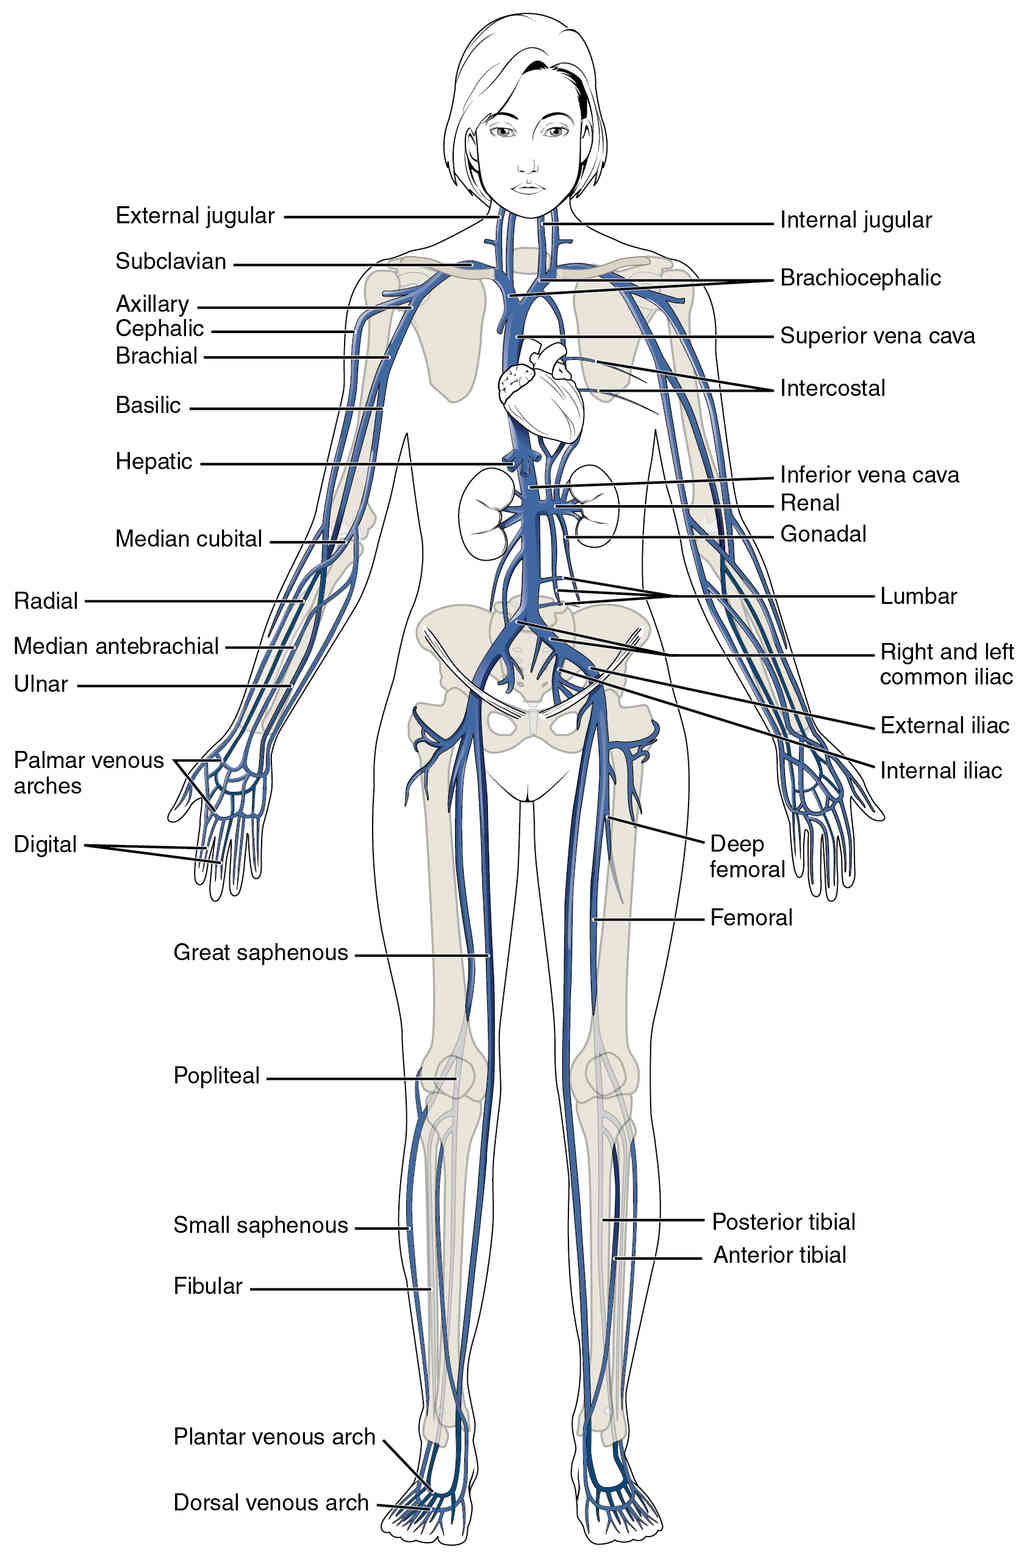

This page is under construction. For now, it is just a resource of the images found in the OpenStax Anatomy and Physiology Handbook. It wil slowly change into a revision tool. Each slide has a number. Use this to refer to the slide. When completed, it will have an unlabelled section, with labelled slides in parallel. On the unlabelled slides, write your answer and use the labelled slide to assess yourself. Keep track by also noting the number on each slide. Improvement at each attempt is important, more so than full marks on a first attempt.